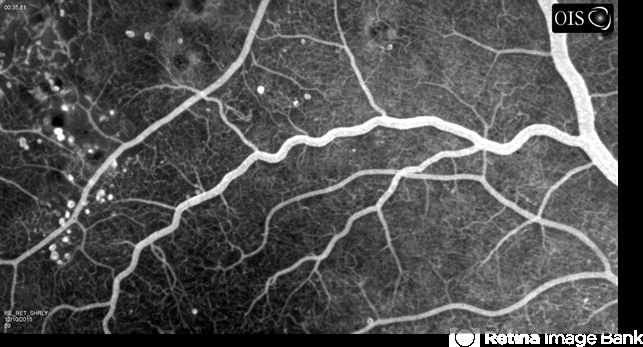

- diabetic macular edema, diabetes, microaneurysms, microangiopathy, tortuous vessels

- Early fluorescein angiogram of diabetic macular edema and tortuous vessels in the superior macula of the right eye.